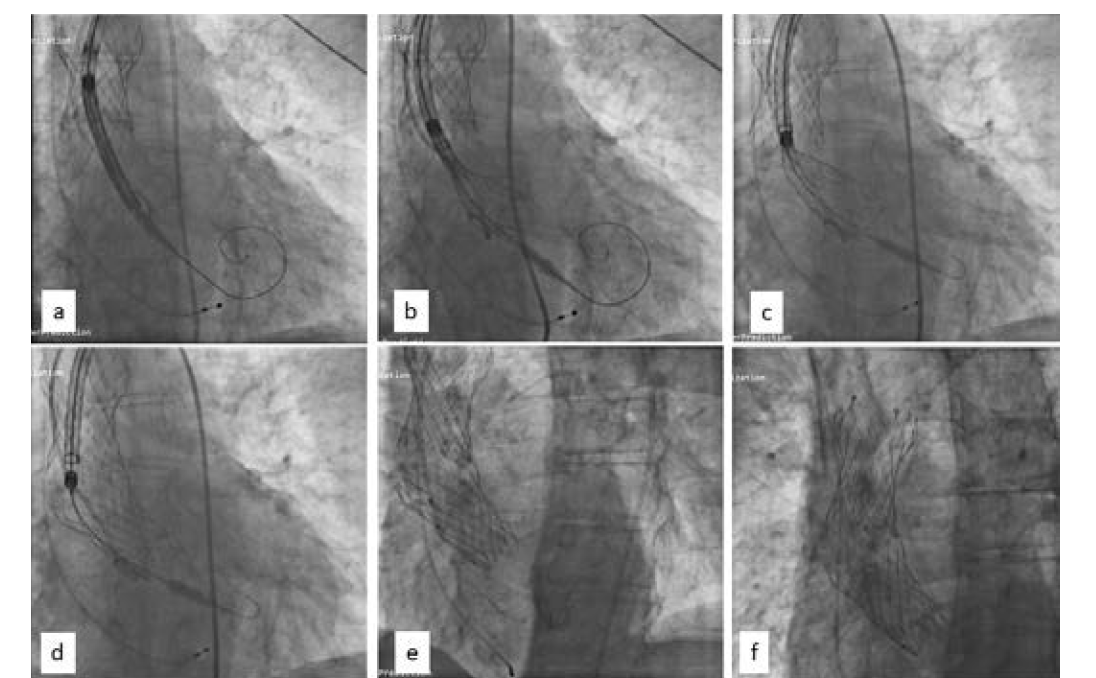

In view of significant stenosis of the lower limb arteries, the patient was prepared for TAVR through a subclavian approach. An 18 Fr DrySeal sheath (Gore Medical) was placed, and a gradient of 76 mm Hg was measured across the aortic valve. Over a Confida Brecker guidewire (Medtronic), a 26-mm Evolut R self-expanding valve (Medtronic) was taken across the aortic valve. Rapid right ventricular pacing was initiated at 180 beats per minute, and the valve was deployed below the aortic annulus (Figure 3a). A chunk of calcium near the noncoronary sinus did not allow the valve to expand (Figure 3b), and immediately after deployment the valve popped out into the ascending aorta (Figure 3c).

There was no coronary obstruction, and the patient was hemodynamically stable. Using a bioptome (Cordis), the valve was pulled high in the aorta, leaving it just proximal to the origin of the brachiocephalic artery (Figure 4). The aortic valve was recrossed and another 26-mm Evolut R self-expanding valve was deployed successfully (Figure 5).